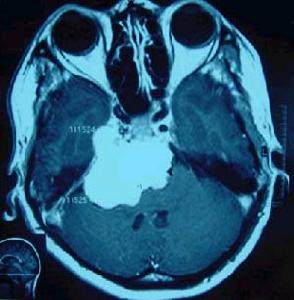

對同一病人,最好問時進行CT和MRI的對比分析。方可得到較正確的定性診斷。這是因為眶腦膜瘤在這兩種圖像中有相類似的表現和特點,而不經加強的MRI會使眶腦膜瘤無法診斷。某些腦膜癌MRI發現不了:1、小的無症狀的眶腦膜瘤不合併水腫和占位效應,尤其是在靠近頂部者;2、多發眶腦膜瘤中小的腫瘤易被遺漏;3、復發腦膜瘤經過注射(GaddoiniumDTPA)造影劑,上述缺點可以得以克服。

眶腦膜瘤MRI圖1、好發年齡不同,膠質瘤多發生於兒童。